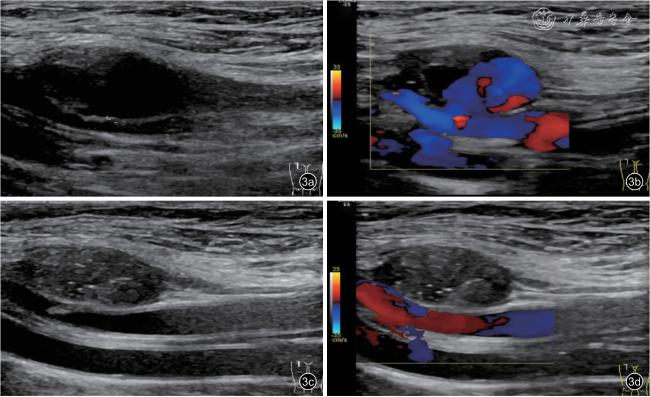

2.假性动脉瘤超声特征收集:采用美国GE LOGIQ E9 超声诊断仪及高频9L 线阵探头(频率 5 ~9 MHz),选择下肢静脉(lower extremity veins,LEV)模式进行操作。患者采用仰卧位,患肢伸直,充分暴露腹股沟术区。术前常规对股动脉穿刺处进行二维超声及彩色多普勒血流成像(color Doppler flow imaging,CDFI)检查,观察假性动脉瘤动脉破口位置,测量有效的瘤腔大小(长径和短径)、破口内径及瘘管长度,测量示意图见图2。脉冲多普勒(pulsed wave Doppler,PW)于破口处可探及高速正负双向动脉频谱,测量破口处峰值流速(peak systolic velocity,PSV)。

图2 股动脉假性动脉瘤超声测量示意图。图a 为模式图;图b 为二维超声图像

注:a 为假性动脉瘤瘤腔长径;b 为假性动脉瘤瘤腔短径;c 为瘘管长度;d 为股动脉破口内径